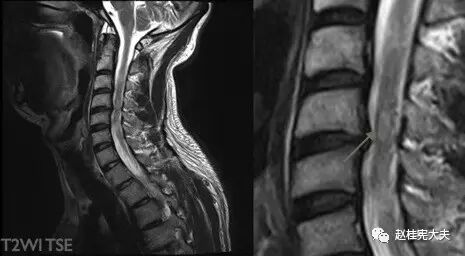

图16. 示C2-6水平颈髓内散在小斑片状T2较高信号,箭头示C4-5水平结节状高信号灶。

图17. 示T5水平胸髓内见短节段椭圆形病灶,T2高信号。

图18. 示T7-8水平胸髓内见条片状T2高信号,且<2个椎体节段。

视神经受侵犯时,呈现T2高信号并可伴视神经增粗,与单纯MS相比,NMO视神经病变范围更广泛,可延伸到视神经后部甚至视交叉,且病变通常呈对称性分布[3];MS脊髓受累者,病灶多>3 mm且<2个椎体节段,横断面上<1/2脊髓面积且水肿轻,而NMOSD脊髓病变可扩展到3个以上脊髓水平,但部分亚洲MS患者的脊髓病灶长度可≥2个椎体节段,AQP4抗体检测有助于鉴别。